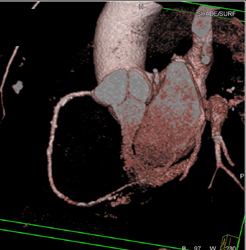

Calcified Bicuspid Valve